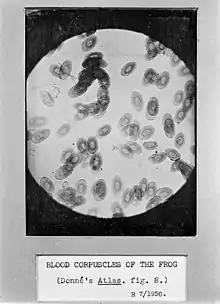

Professor Richard Hill Norris FRSE FRSGS (1830-1916) was a British physiologist, spiritualist and photographer.[1] From the 1880s he began microscopic photography of blood corpuscles and was a pioneer of microphotography. In 1856 he invented the dry collodion photographic plate.[2]

Norris studied medicine at the University of Edinburgh, developing an early interest in microphotography; mainly taking pictures of frogs' blood. In 1856 he invented the first dry collodion photographic plate, during 1858 founding the Patent Dry Collodion Plate Company in Birmingham - one of the first commercial producers of photographic materials in the world.[2]